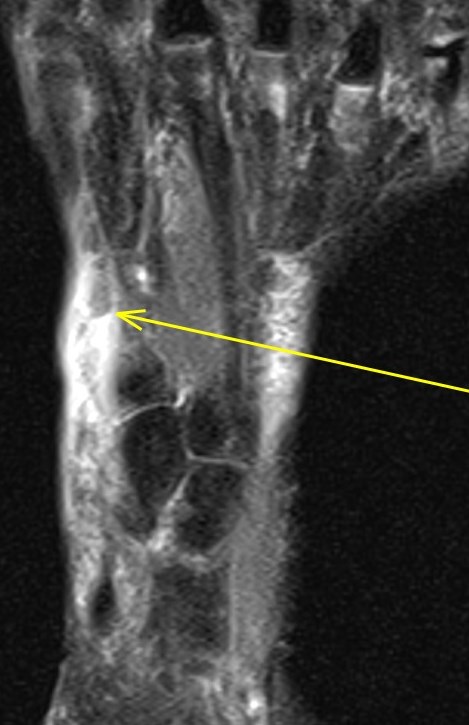

Figure 2 for case Extensor hallucis longus tendon ( RID3188 ) laceration

Figure 2

You can see the cleanly lacerated tendon edges nicely (arrows)